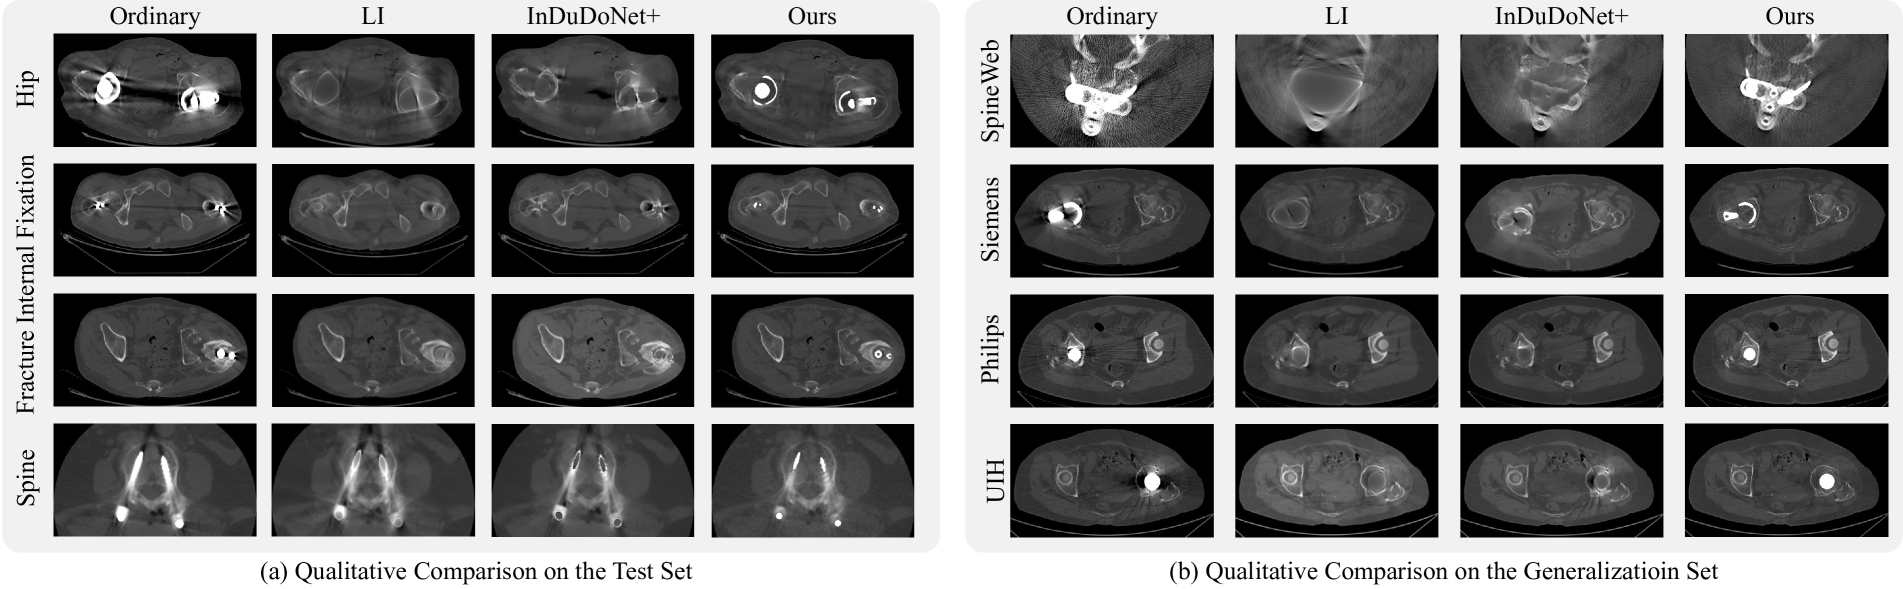

Refer to caption

Figure 4: Qualitative Comparisons. (a) Comparison on the Test Set: Images of patients with hip prostheses used in total hip arthroplasty, fracture internal fixation, and spinal internal fixation. (b) Comparison on the Generalization Set: Evaluation on data from unseen CT machines (SpineWeb dataset, Siemens, Philips, and UIH CT machines) to demonstrate generalization.

Fig. 4 (a) illustrates three types of metal implants. In CT slices with large, bilateral metal regions, the standard sequence exhibits a distinct dark band between the implants, resulting in missing information. Similarly, screw-like implants, although smaller, generate star-shaped artifacts that distort the surrounding tissue. Traditional methods and those trained on synthetic datasets can partially remove these artifacts and restore affected areas, but they often fail to accurately reconstruct the metal implant regions, leading to diminished visual quality. In contrast, our method effectively eliminates these artifacts while preserving the structural details of the implants and restoring the compromised regions. For visualization, we revert the outputs of all models to their original data range using appropriate normalization techniques, and display them with a window level of 500 and a window width of 2000. To demonstrate the generalizability of our approach, we also conducted qualitative comparisons using various ordinary CT machines in Fig. 4 (b). As shown in the figure, even when applied to CT devices not seen during training, our method maintains desired performance, effectively reducing artifacts while preserving structural information. Notably, since these data were acquired from normal CT devices, no ground truth is available for quantitative comparison.